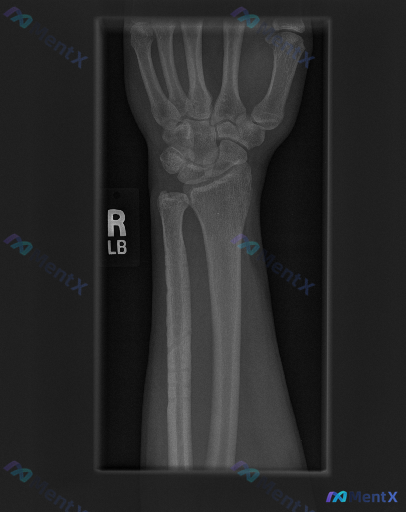

右手腕正位X光片发现异常,除了可见的骨折,还需要警惕哪些方向?

整理到一份右手腕影像学资料及深度评估思路,分享给大家一起讨论。 基本影像表现(右手腕正位X光片) - 骨骼完整性:右侧尺骨茎突处可见明确骨皮质中断,断端有分离移位;桡骨远端关节面、腕骨、掌骨基底未见明确骨折线或骨质破坏。 - 关节与对位:桡腕关节、腕骨间关节间隙清晰,排列大致规则;尺骨茎突骨折处伴随...

整理到一张右侧手腕X光正位片的影像资料,先把关键表现列出来,大家看看这种情况第一反应会往哪些方向考虑? 关键影像表现 1. 骨骼完整性: - 桡骨远端关节面可见横行透亮骨折线,累及关节面,骨皮质不连续,骨折端无明显移位; - 尺骨茎突可见撕脱性骨折征象,骨折块位置清晰; - 舟骨、月骨、三角骨等腕骨...

整理到一份右手及腕关节正位X光片的影像分析资料,分享给大家一起讨论。 影像观察到的关键信息: - 骨骼完整性:桡骨远端、腕骨序列、掌骨及指骨未见明确皮质断裂;但在尺骨茎突部位可见明显的皮质不连续,有一条透亮的骨折线,骨折块有轻微分离移位。 - 关节间隙与对合:桡腕关节、腕中关节及腕掌关节间隙清晰,腕...